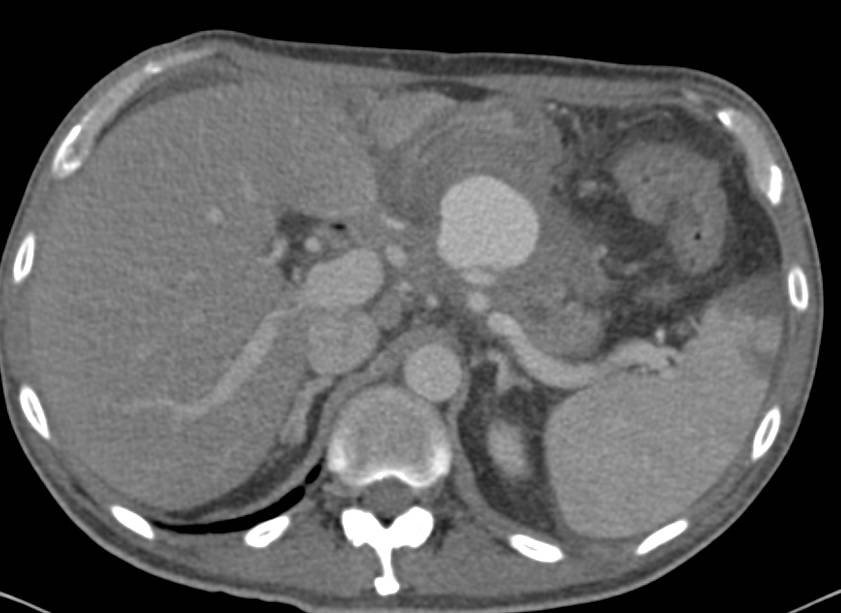

Sarcoidosis Involves the Spleen